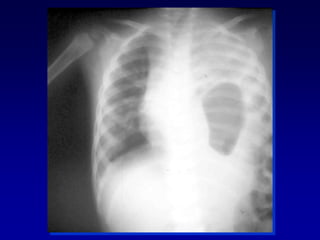

 Trauma alta energía

 > 15 cc/Kg inicial o mayor de 3-4

cc/Kg/hora

 Falla Ventilatoria

 Choque hipovolémico

TRAUMA PEDIATRICO

HEMOTORAX MASIVO